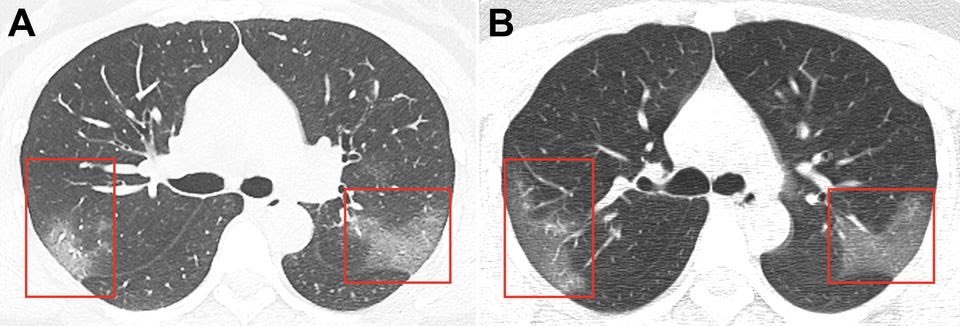

Researchers analyzed scans from patients at the Zhongnan Hospital of Wuhan University, the majority of whom were older men with preexisting health problems. The images above are scans from a 52-year-old patient.

The first group of scans (group A) were taken on January 7, five days after the patient started displaying symptoms. They show patches of ground glass at the bottom of both lungs.

The man was put on life support from January 7 to 12. After that, his condition seemed to improve.

The second set of scans (group B), taken January 21, show that many of the white patches either shrunk or disappeared